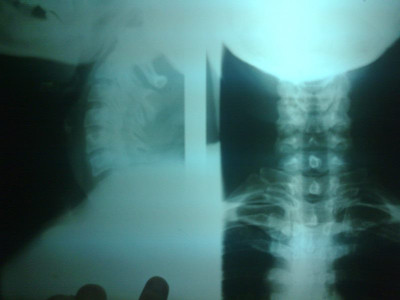

Radiografías con enfoque en fisiatría

Envíado por Dr. Hernán Darío Sánchez Ramos